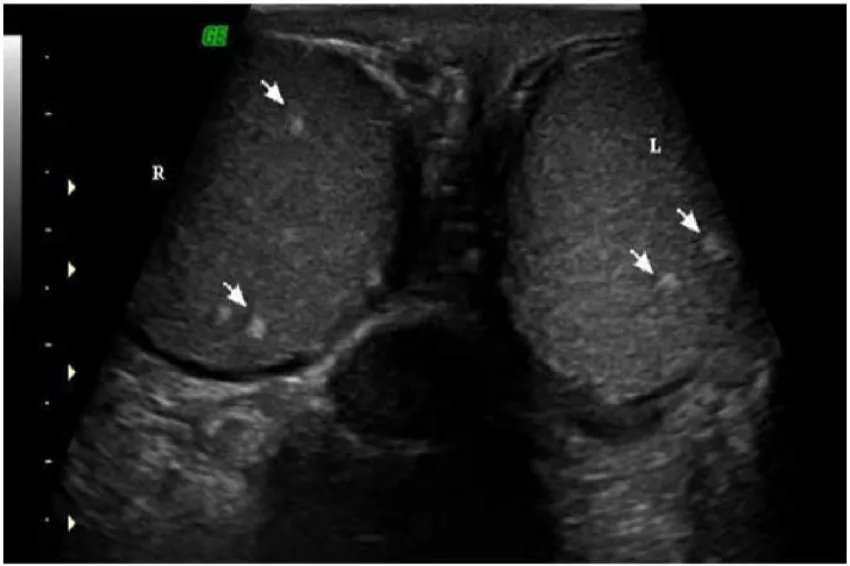

多睾症图片3.隐睾症隐睾也是最常见的先天性睾丸异常。下降过程中停留在腰、腹、腹股沟、内环、腹股沟、外环等任何一个异常的位置,都会变成隐睾。

隐睾症图片4.睾丸萎缩睾丸萎缩出生时很年轻,这是先天因素导致的睾丸萎缩;还有一种可能是后天因素造成的,可能是睾丸感染或外伤造成的,比如供血不足,造成睾丸萎缩。症状1.多睾症从外观上可以看出婴儿不止一个睾丸或腹股沟有肿块。2.隐睾症阴囊内无睾丸,或睾丸偏高,不在阴囊内,但靠近顶部;位于睾丸内环和外环之间;睾丸偏离了从腹腔到阴囊的正常下降路径;睾丸收缩,睾丸和推要么并入阴囊,松驰后收缩至腹股沟,可单侧发生,也可双侧发生。3.睾丸萎缩性器官不成熟、垂体功能减退等。两个睾丸一般都不发达。